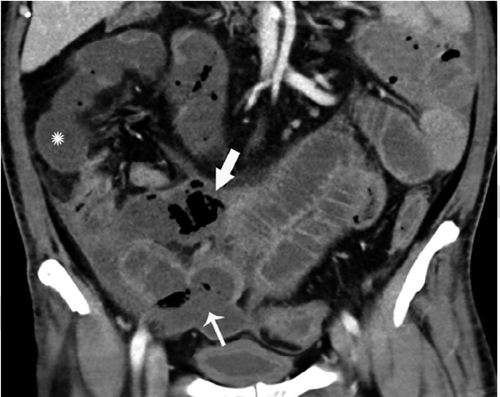

В частности, как пояснил специалист, у некоторых пациентов с COVID-19 внезапно развивался пневматоз - патологическое состояние системы пищеварения, при котором газы проникают в толщу стенки кишечника и образуют там воздушные кисты. Кроме того, у нескольких людей было выявлено необычное желтое обесцвечивание кишечника, еще у трех больных - инфаркт кишечника.

© Radiology